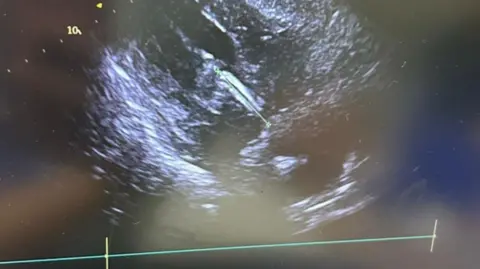

The device sits inside the left ventricle and works by temporarily taking over the function of the heart to provide it with strong blood pumping pressure to ensure sufficient blood flow to the heart muscle while it is operated on.